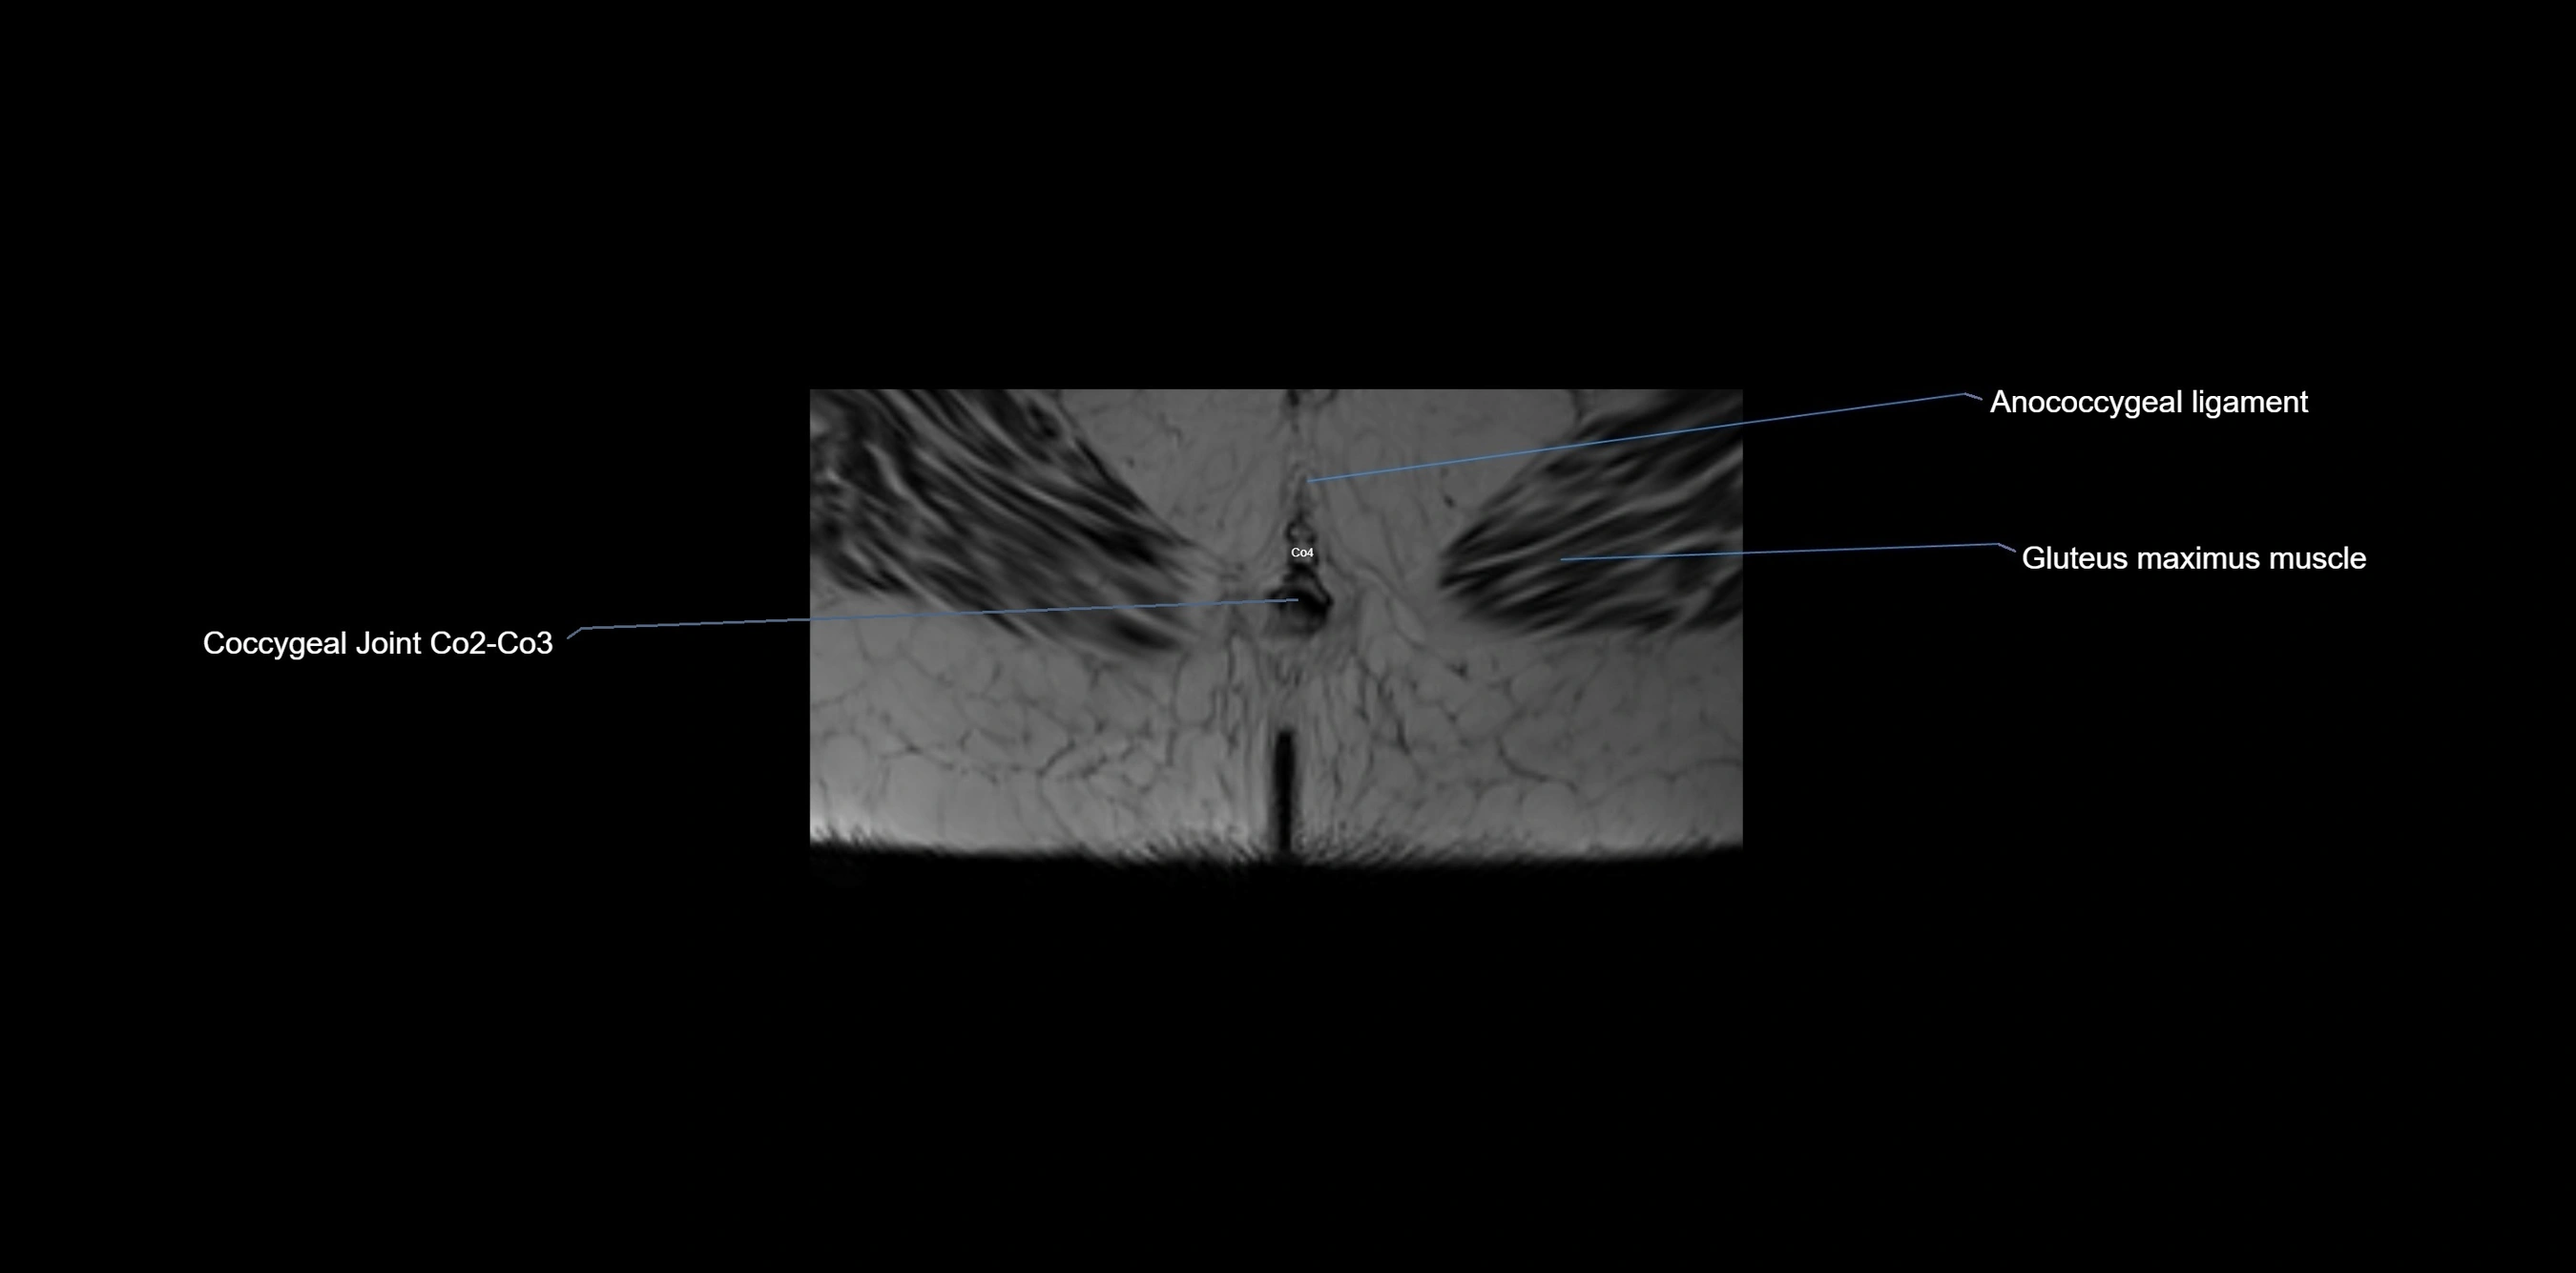

CT VRT image

image